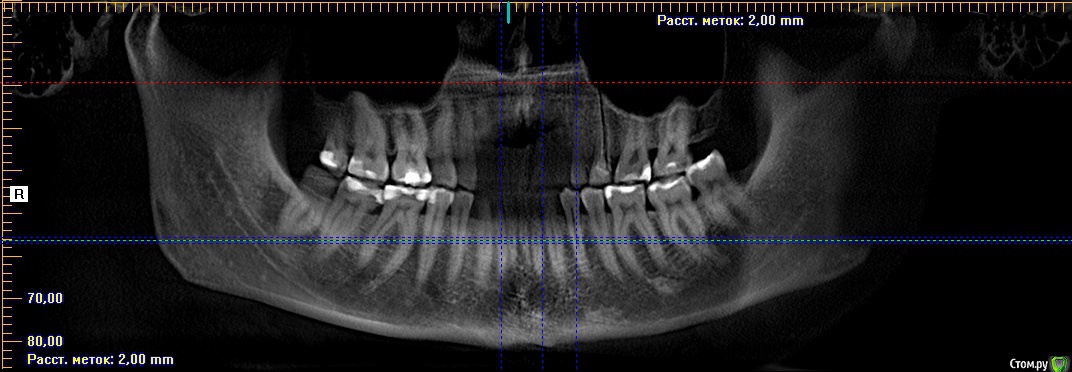

barvika Опубликовано 21 сентября, 2016 Поделиться Опубликовано 21 сентября, 2016 Здравствуйте. Для решения вопроса по имплантации 21 зуба по старым штифтом и гранулемой было сделано КТ. Доктор на КТ кроме этого зуба ничего критичного не увидел. Но я, внимательно рассмотрев снимок, заметила светлое пятно под 1ым моляром слева. Приблизительно на этом месте в самой ротовой полости на десне маленький твердый выступ, немного острый, размером не более 1 мм.Обратила внимание хирурга на это пятно, он рассмотрел, сказал , что его видно только на орто, в 3d не видно,что сама кость ровная. Вообщем, обнадежил меня ,что ничего страшного, просто уплотнение кости и ничего с этим делать не надо, только повторить КТ через год. Но я еще тот паникер, уже накрутила себя.Снимки приложила, есть еще на диске само КТ, но не знаю, какие файлы из него нужно выложить.Посмотрите, пожалуйста. Спасибо. Ссылка на комментарий

barvika Опубликовано 22 сентября, 2016 Автор Поделиться Опубликовано 22 сентября, 2016 Спасибо Вам! Только я просчиталась, пятно под первым моляром на нижней челюсти слева. Прошу прощения за ошибку. Ссылка на комментарий

red_butler Опубликовано 22 сентября, 2016 Поделиться Опубликовано 22 сентября, 2016 Спасибо Вам! Только я просчиталась, пятно под первым моляром на нижней челюсти слева. Прошу прощения за ошибку.приглядитесь, справа тоже есть, считайте это "родимыми пятнами" Ссылка на комментарий